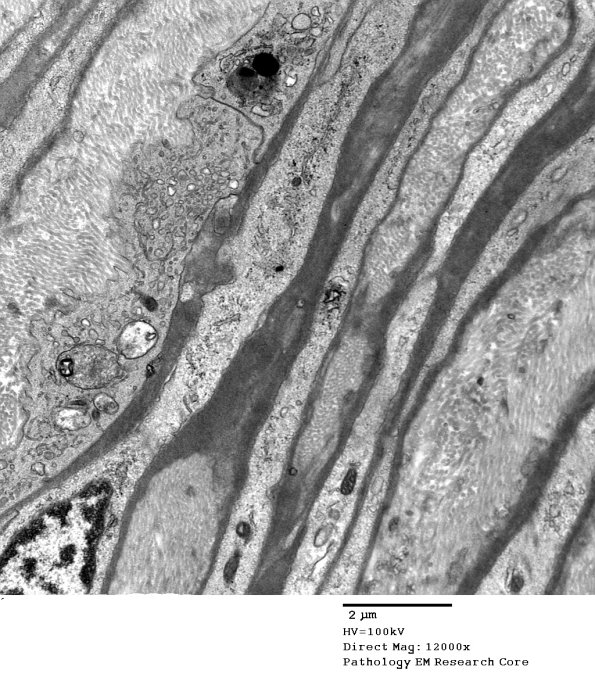

11D1-3 The surrounding perineurium appears hyperplastic with increased cytoplasm including increased numbers of mitochondria in perineurial processes(?). (electron micrographs)